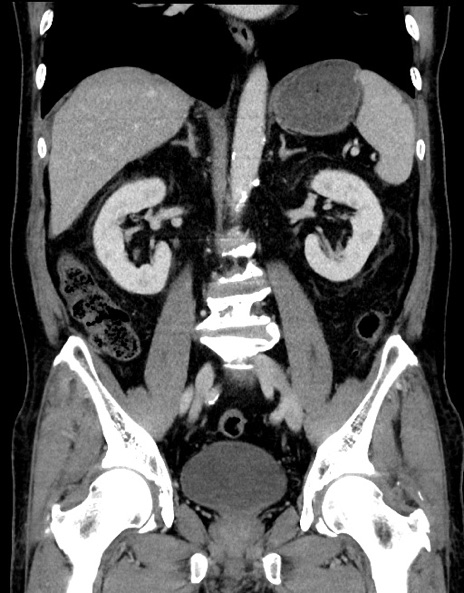

症例15(冠状断像)

【症例】70歳代男性

【主訴】腹痛

【現病歴】今朝から腹痛あり。全体的に痛い。特に左上の方。排ガスが今日はない。冷や汗が出る。

【既往歴】直腸癌術後

【身体所見】左側腹部〜上腹部に圧痛あり。腹膜刺激症状明らかなではない。軽度反跳痛。左下腹部に術後瘢痕あり。

【データ】WBC 7700、CRP 0.02